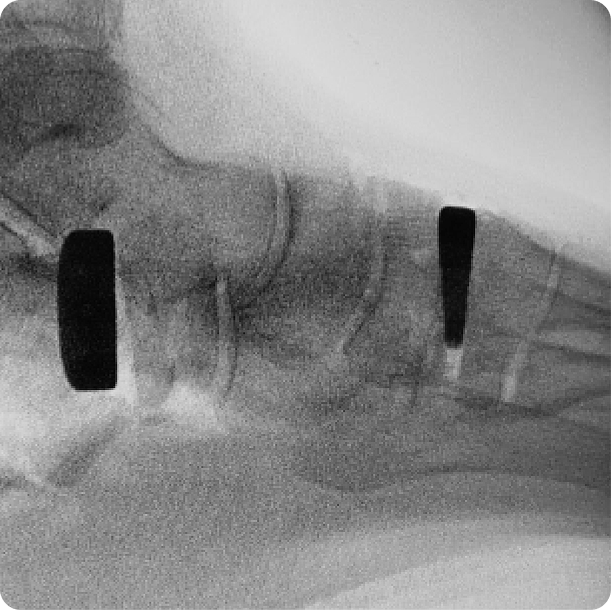

CUÑAS DE ALARGAMIENTO Y COTTON

Dentro de las múltiples patologías que se producen, la deformidad en pie plano (pie plano valgo del adulto) es una de las más relevantes, complejas y en continuo cambio e innovación.

El tratamiento quirúrgico del pie plano valgo rara vez precisa un solo procedimiento aislado, sino más bien una selección de técnicas. Entre estas técnicas, las osteotomías de Alargamiento y Cotton ocupan un lugar importante.

• Osteotomías de apertura con cuña de los huesos del pie (osteotomías incluidas para la corrección de juanetes).

• Apertura con cuña del cuneiforme medial u osteostomías de Cotton.

• Alargamiento de la columna lateral (osteotomía en Z del calcáneo).

• Artrodesis metatarsiana/cuneiforme.